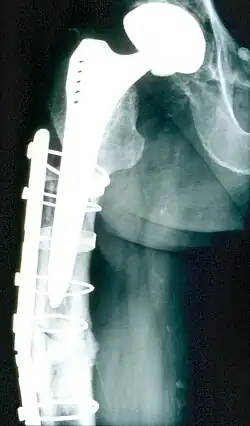

Hüfte

Als Vorläufer der heutigen endoprothetischen Technik gilt der 1939 publizierte[3] partielle Hüftkopfersatz durch „Cup-Plastik“[4] nach Marius Nygaard Smith-Petersen. Den ersten totalprothetischen Ersatz (mit Endoprothese und neuer Pfanne) führte John Charnley 1961 ein. Pioniere der Hüftendoprothetik in Deutschland waren in den 1960er Jahren Hans-Wilhelm Buchholz und Hans-Hermann („Peter“) Lubinus. Werden sowohl der Gelenkkopf als auch die Gelenkpfanne ersetzt, handelt es sich um eine Total-Endoprothese (TEP) der Hüfte (Hüfttotalendoprothese, HTEP, genannt auch Hüft-TEP). Wenn nur der Hüftkopf ersetzt wird, ist das eine Hemi-Endoprothese (HEP).

Operative Behandlung

Die Operation kann sowohl unter Vollnarkose als auch mit einer Spinalanästhesie durchgeführt werden. Zunächst werden die verschlissenen Gelenkoberflächen und der bisherige Gelenkkopf am Oberschenkel entfernt und der verbleibende Knochen für das Implantat vorbereitet. Danach erfolgt die Implantation und Verankerung der beiden Gelenkkomponenten mit den oben beschriebenen Alternativen.